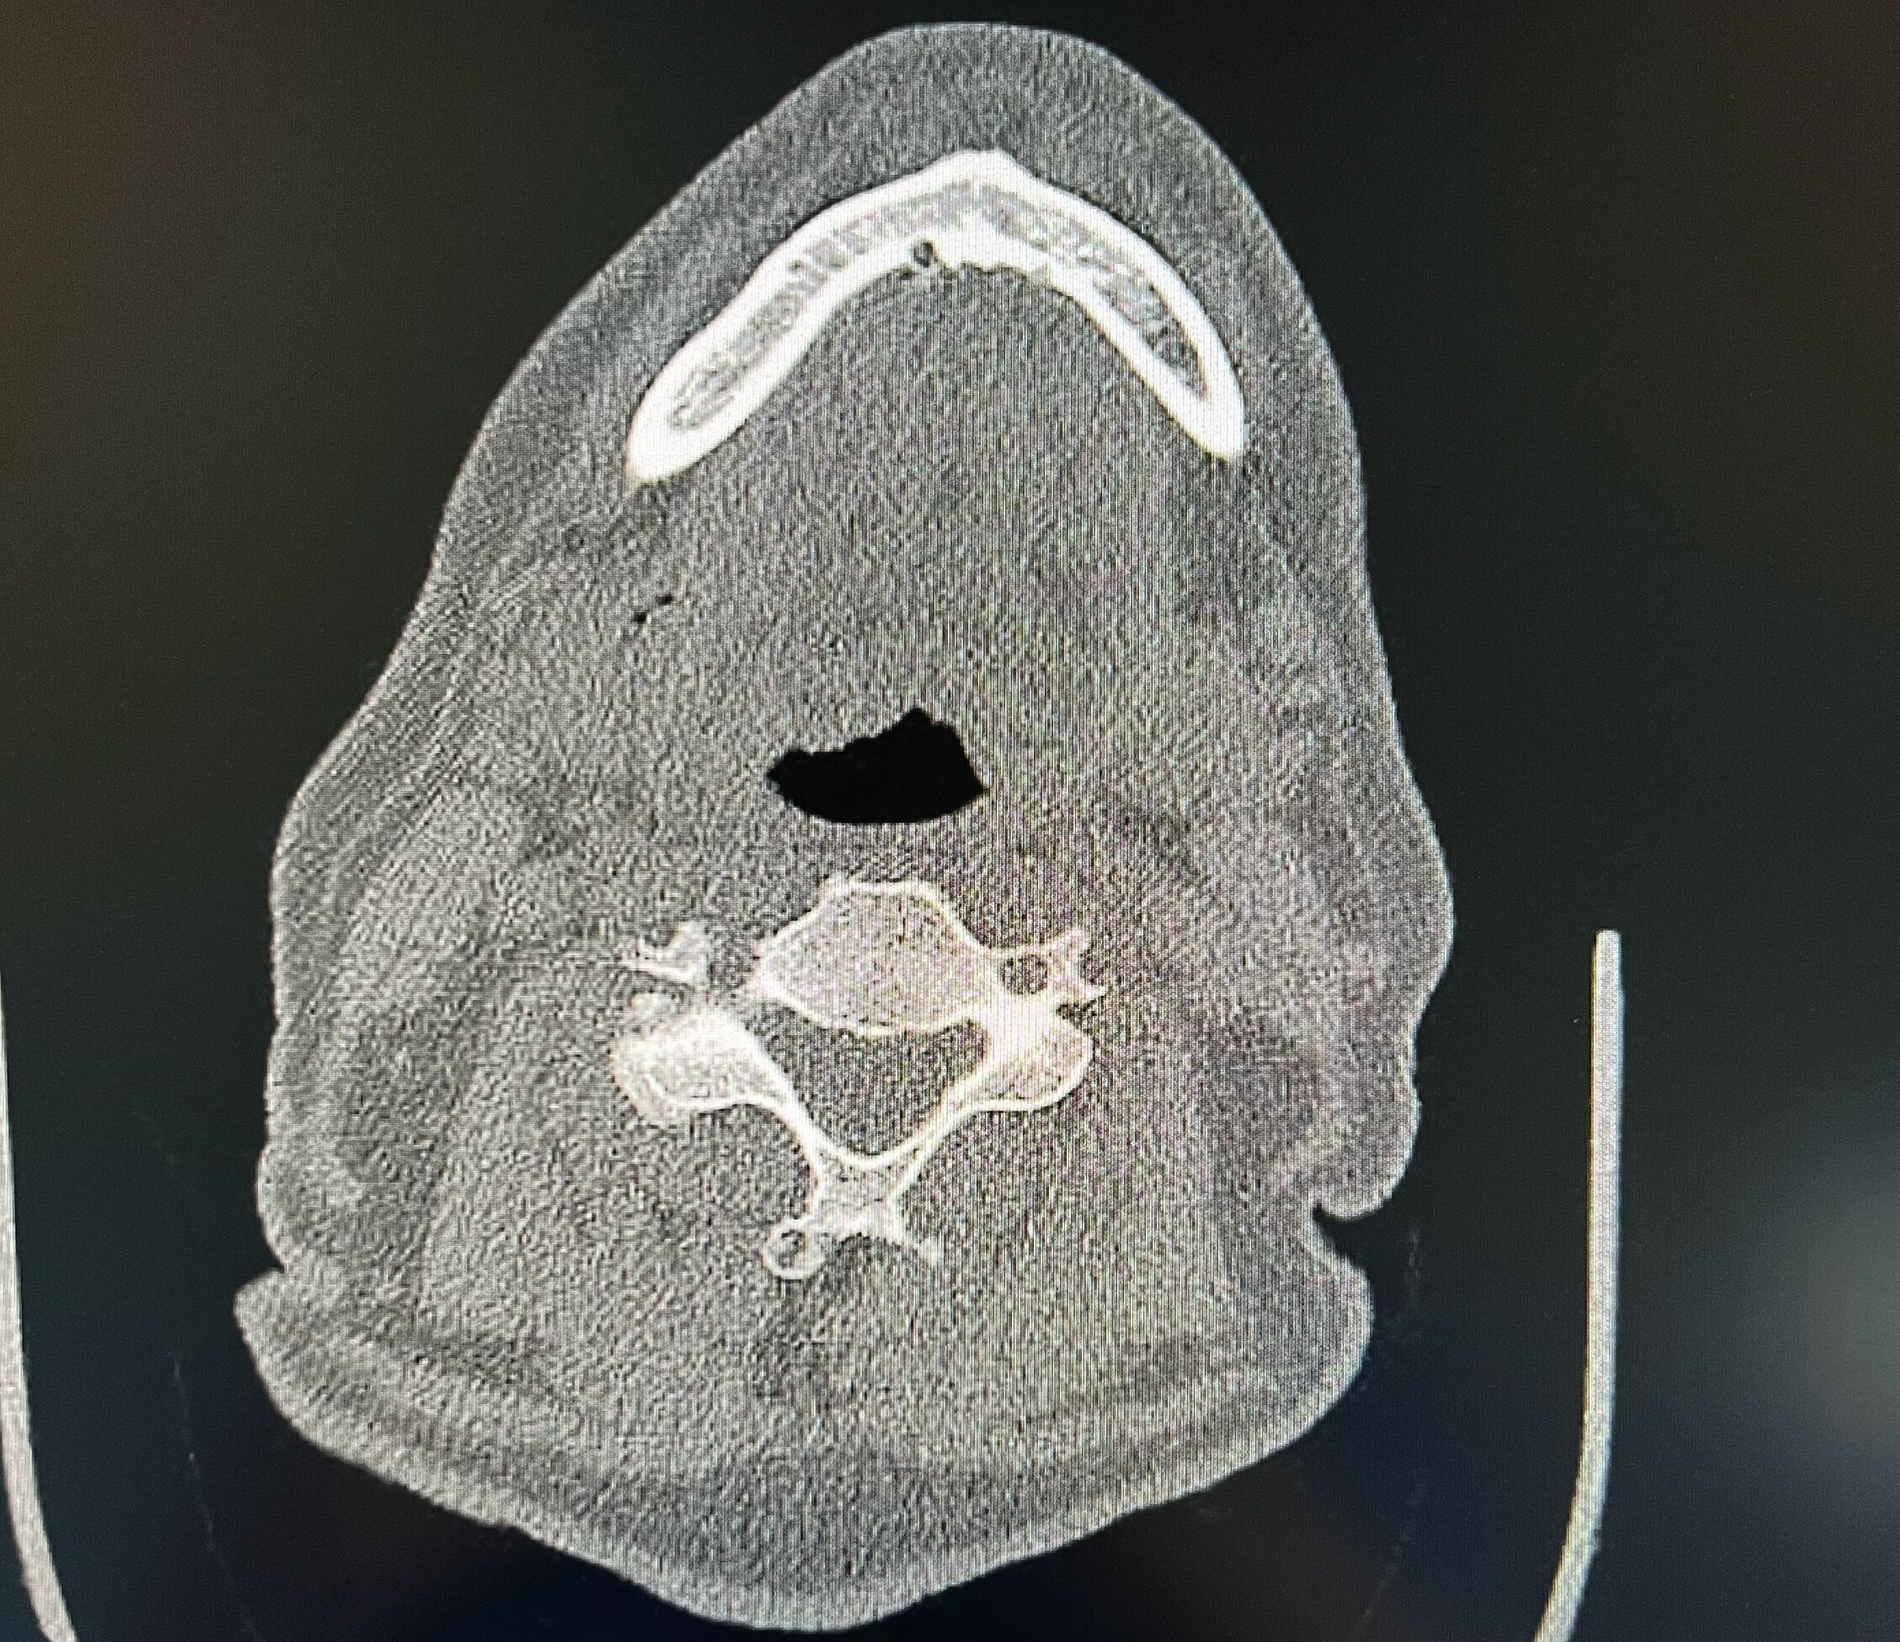

Ein vom Patienten mitgebrachtes DVT (Digitale Volumentomografie) zeigte die nach lingual in den Mundboden ragende Implantatspitze regio 43 (Abbildung 2). Die im Rahmen der weiterführenden Verlaufsdiagnostik durchgeführte Computertomografie (CT) konnte dies bestätigen und zudem ein massives Hämatom im vorderen Mundboden mit Ausbreitung in Richtung des zervicalen Halsweichgewebes darstellen (Abbildung 3). Eine aktive Blutung sowie eine Komprimierung der Atemwege konnten radiologisch ausgeschlossen werden. Der Patient wurde nach Abschluss der klinischen und radiologischen Untersuchung zur Überwachung stationär aufgenommen.